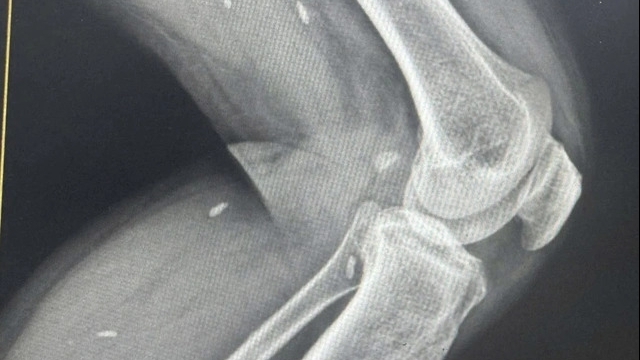

Bằng sự cố gắng cùng sự chuẩn bị trước mọi tình huống có thể xảy ra, ca phẫu thuật diễn ra an toàn, bé trai chào đời với cân nặng 3.580 gram. Về phía sản phụ, phần bánh rau không bong được cài răng lược đâm xuyên thành bàng quang làm rách vùng đáy bàng quang, khiến bàng quang chảy máu. Các bác sĩ đã tiến hành cầm máu bàng quang, cắt bán phần thấp tử cung và xử trí các tổn thương.